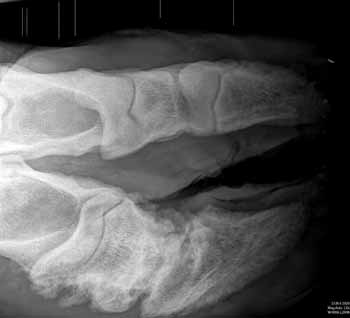

The valuable stock bull, Bennant William had been examined by the vet who was not optimistic about his prognosis and was recommending that Mr Collingbourne consider putting the animal down. The vet in question did not think it possible to X-ray a bull and without knowing what was going on inside the foot, could not suggest any suitable treatment.Mr Collingbourne had read an article about Equirays new ambulatory X-ray service in the newspaper and called director Beryl Williams to see if she thought they could help. Equiray took advice from its own veterinary contacts and used a bull crush supplied by Geoff Watkins from Bwlch, a contract foot trimmer, to keep the animal still during the procedure. Digital X-rays were quickly acquired by the skilled technician using Equirays portable imaging device and given directly to the vet on a memory stick for him to review.

The images showed that a foreign object had entered the foot, causing infection and discomfort. However, with plenty of rest and as the injury started to heal over, Bennant William started to place the foot to the floor and is now 90% back to full health.